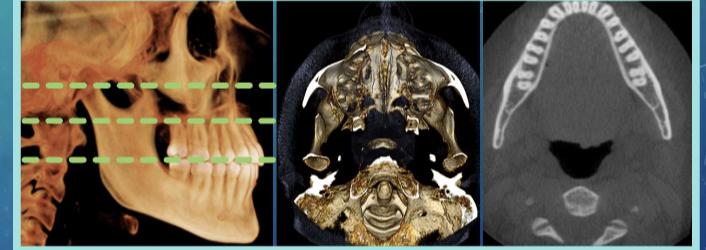

CBCT scan - cone beam, computed tomography

cone-shaped x-ray beam, rotates around the patients head

spatial res - voxels 3-dimensional pixels

Coronal plane

axial plane

sagittal plane

anatomical/ orthogonal projections

multiplanar reconstruction/ reformation

volumetric rendering